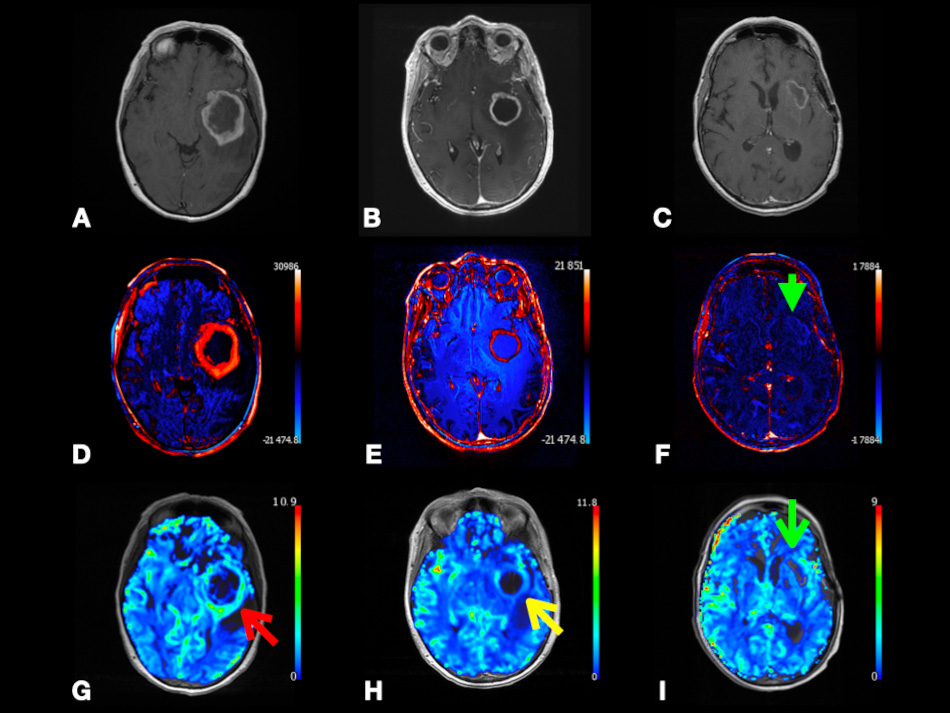

In Fig. 8, we present a case of right frontal lobe non-small cell lung cancer MT. Color-coded CBF map from pcASL data and color-coded rCBV map from DSC data show heterogenous hyperperfusion amongst nodules at super lesion margin and enhancing margins elsewhere. This demonstrates that MTs may show hyperperfusion using ASL or DSC. This highlights the importance of using quantitative parameters, such as tumoral and peritumoral CBV and CBF to compare between GBM and MTs as depending on observing hyperperfusion signals on the color-coded maps is subjective and can be misleading.

Fig. 8.Right frontal lobe non-small cell lung cancer metastasis. Axial SWI (A), FLAIR (B), and post-contrast T1-weighted (C) images depicting lesion with heterogenous enhancement, perilesional vasogenic edema, central necrosis, and intralesional hemorrhage. Axial pcASL source data (D), color-coded CBF map (E) from pcASL data, and color-coded rCBV map (F) from DSC data depicting heterogenous hyperperfusion amongst nodules at super lesion margin (red arrowheads) and enhancing margins elsewhere (yellow arrowheads). Abbreviations: SWI, Susceptibility weighted imaging; FLAIR, Fluid attenuated inversion recovery; pcASL, Pseudo-Continuous Arterial Spin Labeling; CBF, cerebral blood flow; rCBV, relative cerebral blood volume; DSC, Dynamic susceptibility contrast MR imaging.